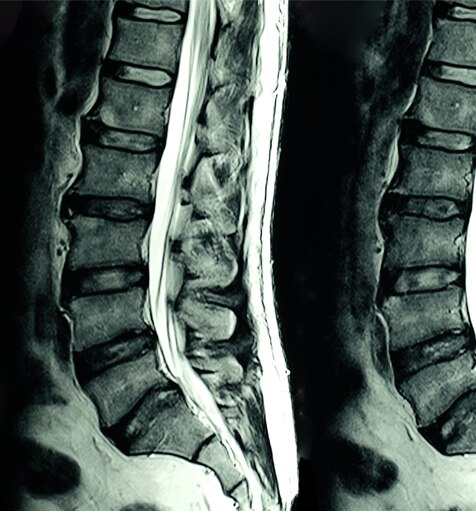

Die MRT (Magnetresonanztomographie) ist eine nicht-invasive Scan-Technologie, die Schnittaufnahmen des Körpers produziert. Sie kommt in einer Reihe von medizinischen Fachgebieten zum Einsatz, z. B.: Muskel-Skelett-Erkrankungen, Gastroenterologie, Onkologie, Herz- und Gefäßheilkunde und neurologische Bildgebung. MRT-Scans können Weichgewebestrukturen in beliebigen Ebenen differenzieren, was sie zu einem unverzichtbaren Diagnosewerkzeug macht.

MRT-Scanner erzeugen ein starkes Magnetfeld, das in Verbindung mit Hochfrequenzströmen verwendet wird, um spezifische Moleküle im Körper anzuregen.

Anhand des Verhaltens dieser Moleküle kann ein dreidimensionales Bild von Körpergewebe erzeugt werden. Beispiele für MRT-Bilder finden Sie nachstehend: